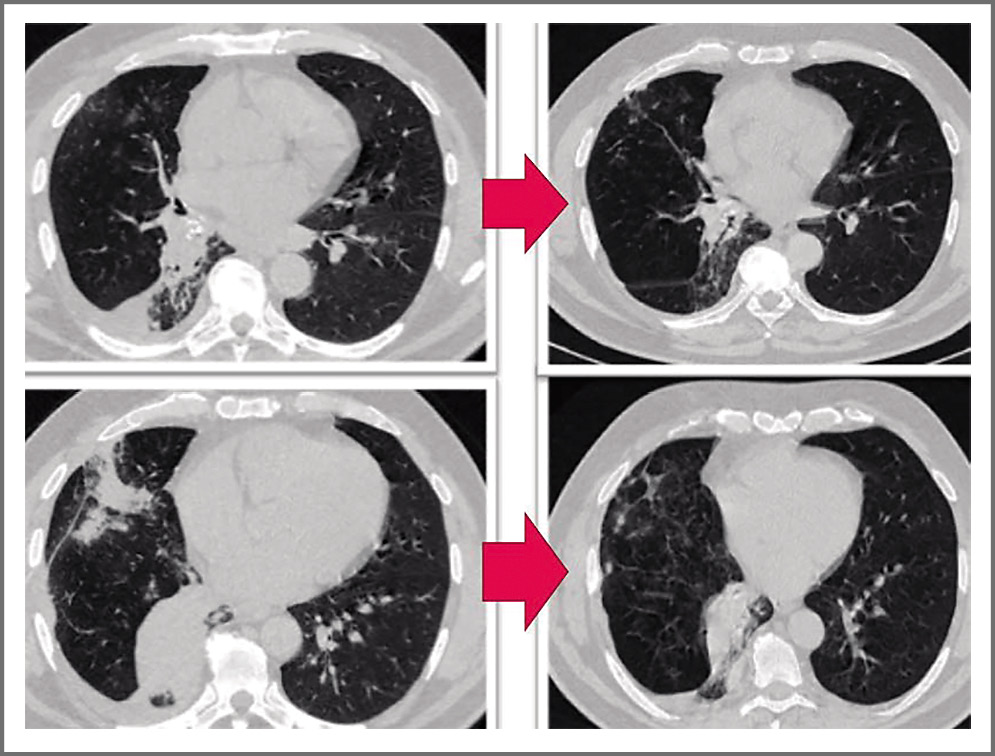

После проведения курса рекомендованной терапии пациент повторно обратился в Центр диагностики и реабилитации заболеваний органов дыхания ФГБНУ ЦНИИТ, где была выполнена КТ ОГК (03.06.2020); рис. 1.

Рис. 1. При сравнении данных КТ ОГК от 14.02.2020 и от 03.06.2020 (слева направо) выявлена положительная динамика в виде рассасывания очагов и уменьшения фокусных образований в средней и нижней долях правого легкого.

Fig. 1. When comparing the chest CT of 14.02.2020 and 03.06.2020 (from left to right), positive dynamics was revealed in the form of resorption of foci and a decrease in focal formations in the middle and lower lobes of the right lung.

Клиническая ситуация обсуждена совместно с ведущими специалистами Центра диагностики и реабилитации заболеваний органов дыхания ФГБНУ ЦНИИТ: с учетом клинической картины (выраженный, сохраняющийся более 1 года приступообразный кашель), данных КТ ОГК в динамике (положительная динамика после курса АБТ, сохранение ателектаза нижней доли правого легкого с признаками обтурации просвета промежуточного бронха справа), отсутствием признаков атипии в гистологических препаратах двух бронхобиопсий сохранялось подозрение на наличие инородного тела в области базальных бронхов справа. Однако из-за лимфаденопатии средостения оставалась и онконастороженность. Учитывая вышеизложенное, принято решение о проведении бронхоскопического исследования (криобиопсии и/или криореканализации) в условиях наркоза.